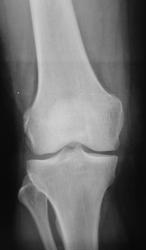

Травма. Пациент направлен на рентгенографию коленного сустава.

Пациент направлен на рентгенографию коленного сустава.

Определяется уплотнение кортикального слоя суставных поверхностей, заострение межмыщелковых возвышении, слабовыраженная краевая  костная деформация - по совокупности   тянет на ДОА I ст. Ну, а то, что на прицельной то это - игра теней - мое мнение.

Прицельных снимков не делали, это обычных два снимка на цифре.

ДФА 1

артроз пателло-феморального суставчика и лигаментоз крестовидных связок.